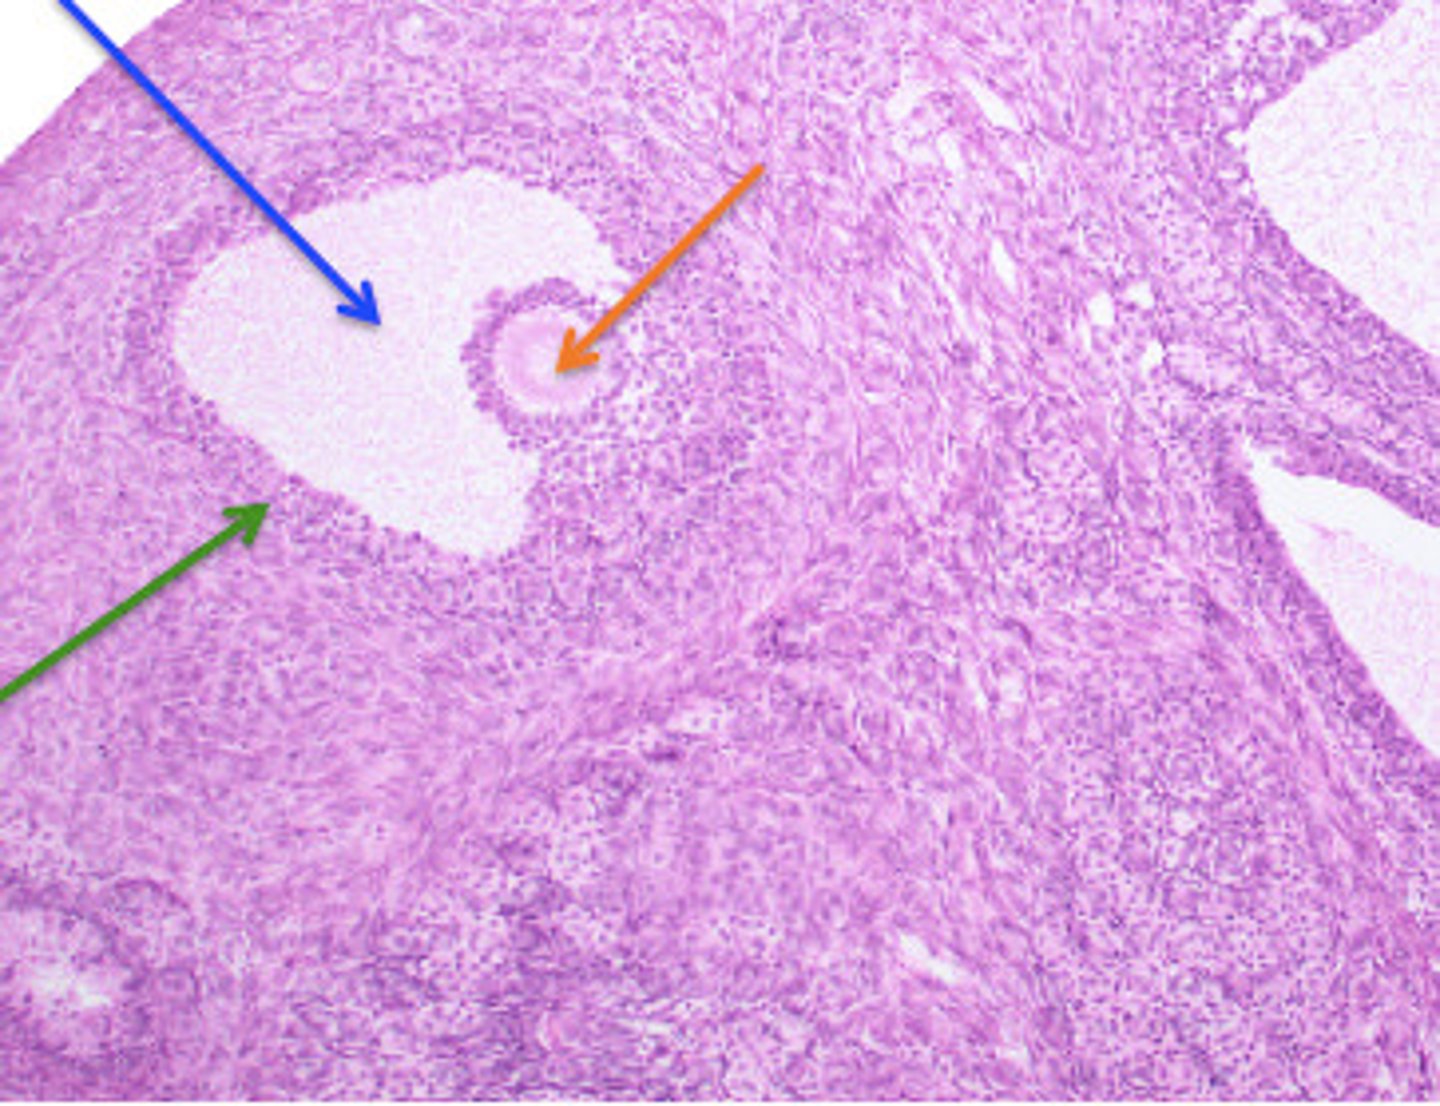

Testes: Testosterone, Inhibin

Both produced in Interstitial Cells of the testes

Name this gland and hormones produced (and location)

Seminiferous Tubules

Identify the structures